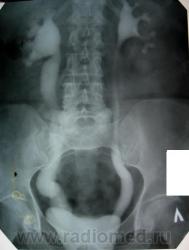

1. Имело место выпадение матки, все виденное - следствие этого прооцесса (кстати, больная была прооперирована, работает, а поступила сейчас с МКБ).

2. Если присмотреться к снмку на 27 мин стоя и на 120 к нижнему краю мочевого пузыря (хоть и под срез пленки), то кое что из этого можно было бы заподозрить.

4. Сегодня проведена в\в урография, двусторонний, больше справа, уретерогидронефроз сохраняется, динамика за 12 лет умеренно отрицательная. Д мочеточника справа до 4,0 см. Дистальные отделы мочеточников конусовидно сужены (слева видно лучше) на протяжении до 1,0 см или несколько более.

5. Прооанализировав повторно картину, оценив анамнез пришел к выводу о неправомочности первого вывода о причине изменений. Да, выпадение матки усугубило процесс, но он существовал и РАНЕЕ...очень много лет. Считаю, что имеет место АХАЛАЗИЯ мочеточников и, следовательно, Владимир Васильевич был прав. Вероятность того, что пусковым механизмом была ЧМТ весьма высок, хотя не исключаю и врожденный характер.